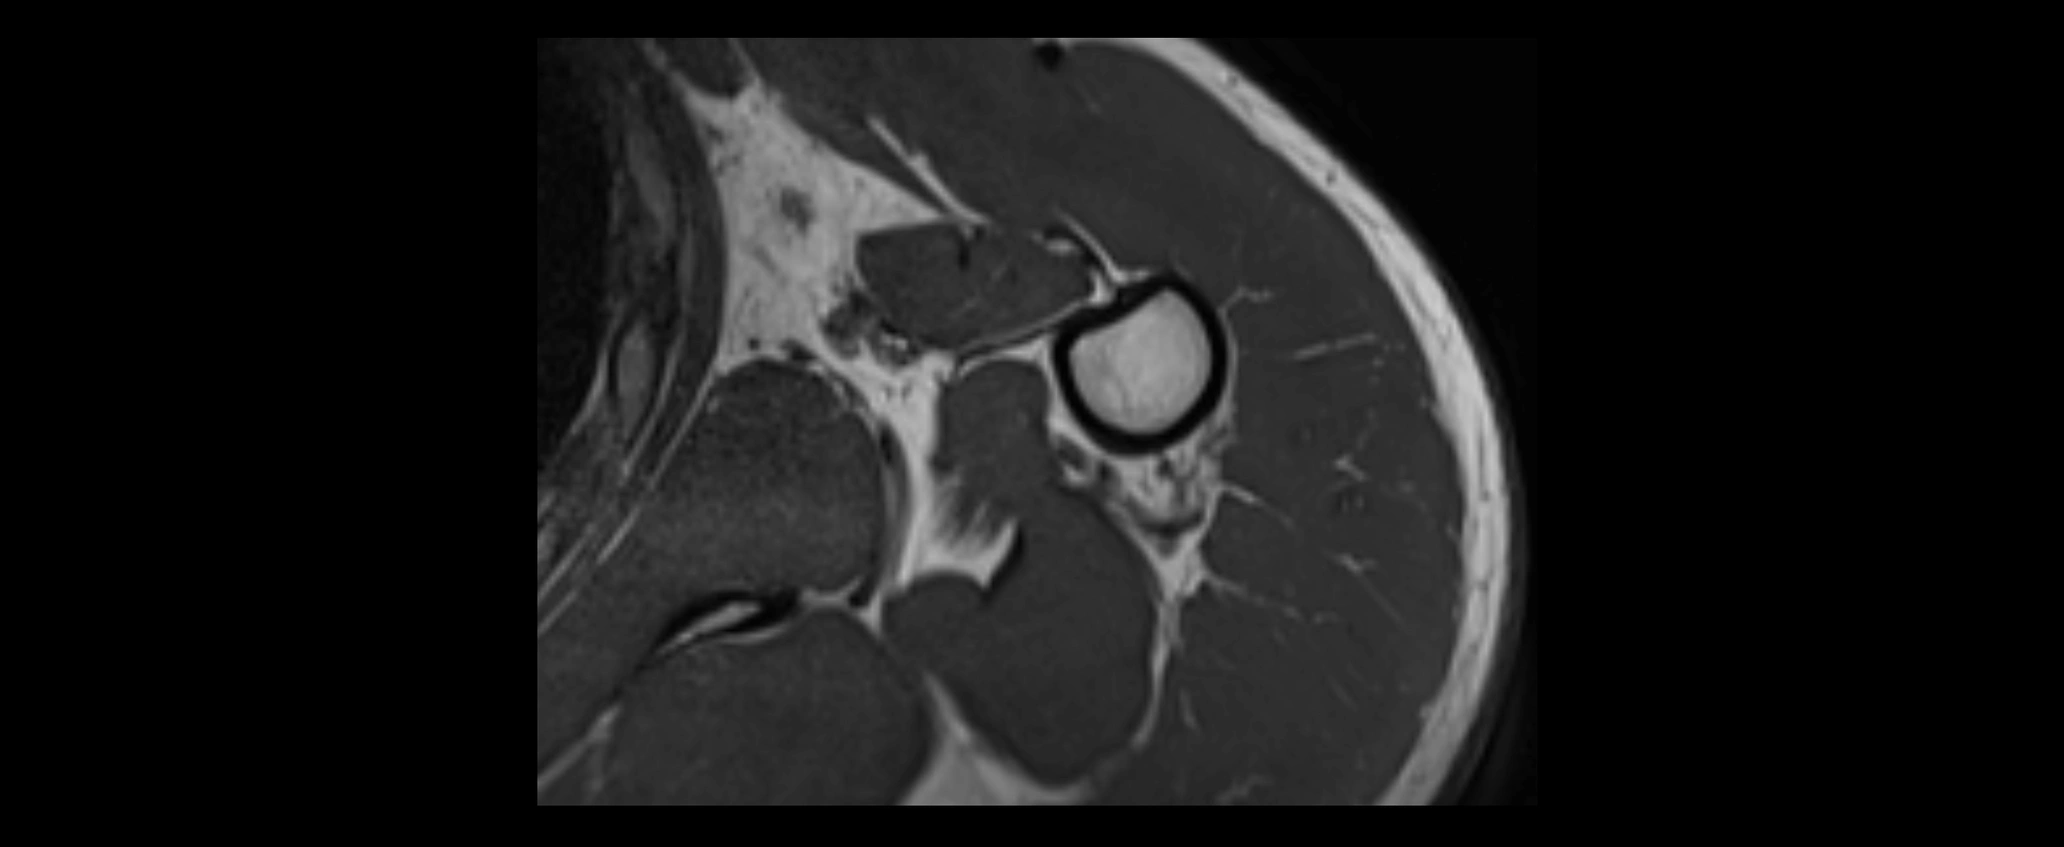

MRI images

image

• Proton Density Fat-Saturated (PD FS):

• Normal ligament: Low signal, uniform thickness.

• Partial tear or sprain: Bright signal or contour irregularity.

• Complete tear: Clear discontinuity with bright signal gap and joint effusion.

• Excellent for assessing joint capsule, coracoclavicular ligaments, and periarticular edema.